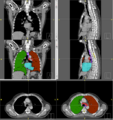

File:RadOnc LU seg.png

RadOnc_LU_seg.png (513 × 545 pixels, file size: 197 KB, MIME type: image/png)